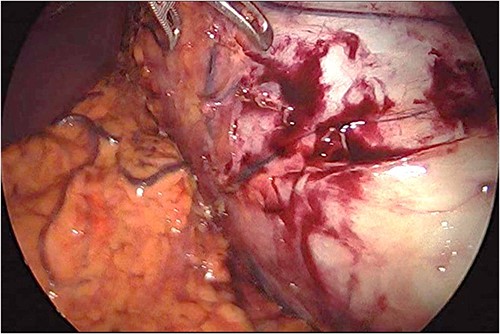

Preoperative prophylactic antibiotics and anticoagulant were given upon induction of anesthesia. The abdomen was accessed safely using a 5-mm vesiport under the guidance of the camera to the left and above the umbilicus. The remaining ports, a 15-mm port 5 cm at the right and above the umbilicus, a 5-mm ports at the left upper quadrant and 5-mm ports at the right upper quadrant were placed with no issues. The cyst was located at the lower pole of the spleen (Fig. 3). The operation consisted of opening the cyst and aspirating dark fluid, removal of the cyst wall (Fig. 4), cauterizing the part of the cyst adherent to the spleen, packing the surgical area with the omentum and removal of the specimen (Fig. 5). The postoperative period was uneventful. The final pathology showed a cyst wall lacking epithelial lining confirming the diagnosis of a pseudocyst, and the cystic fluid showed no malignant cells.